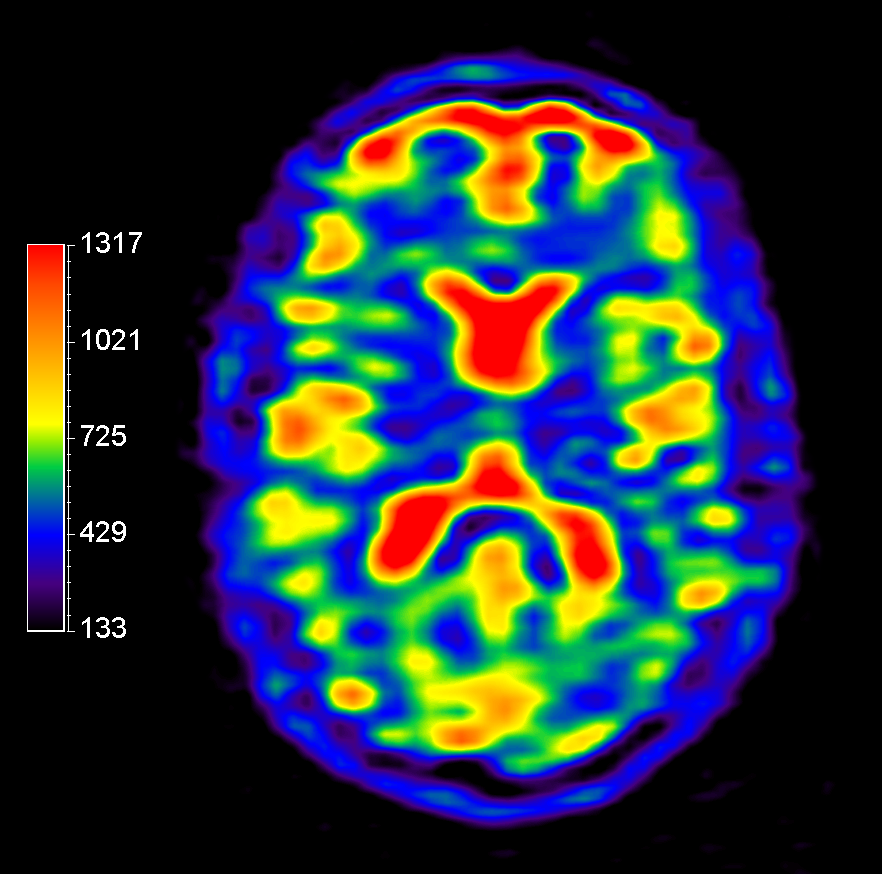

23Na bFFE (axial reformat)

Multi Nuclei - Brain imaging (23Na)

Make multi-nuclei imaging and spectroscopy become part of your clinical operations via a seamless integrated workflow for multi-nuclei image acquisition, spectroscopy, reconstruction, and viewing. The nucleus is just a scan parameter like any other sequence parameter. A single ExamCard can be used to run both proton and non-proton imaging. Reconstruction and viewing of non-proton images or spectra, as well as the process for sending the data to PACS is fully integrated, so workflow does not differ from proton imaging. The dual tuned head coil from Rapid biomedical is immediately recognized by the ExamCard interface and your full brain exam, including acquisition of proton and other nuclei, can be completed without switching coils.